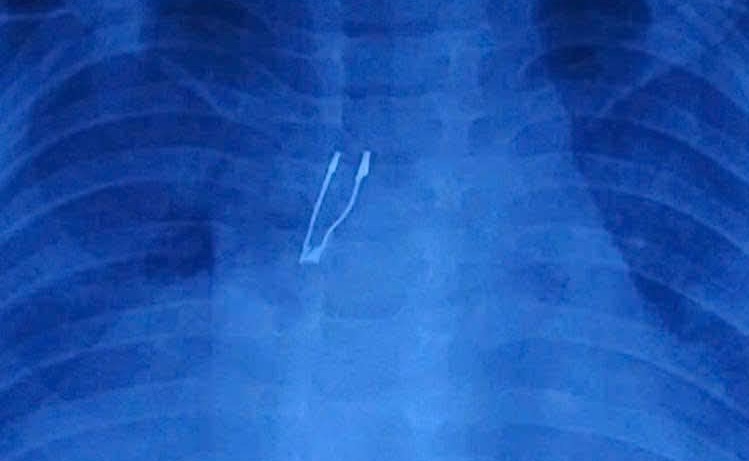

X-ray results revealed a radiopaque foreign object in the right main bronchus, accompanied by partial right lung collapse and mediastinal emphysema. Recognizing the complex situation, Doctor Vinh and the anesthesia team immediately performed emergency airway endoscopy.

Image of the foreign object on an X-ray film. Hospital provided |

Image of the foreign object on an X-ray film. Hospital provided

The foreign object was identified as an LED bulb, deeply embedded in the bronchus. According to Doctor Vinh, removing the object was particularly challenging due to the extremely small airway of a 9-month-old child. The bulb's wide, sharp base made it prone to getting stuck when pulled through the larynx, potentially causing mucosal tears or lodging between the vocal cords.